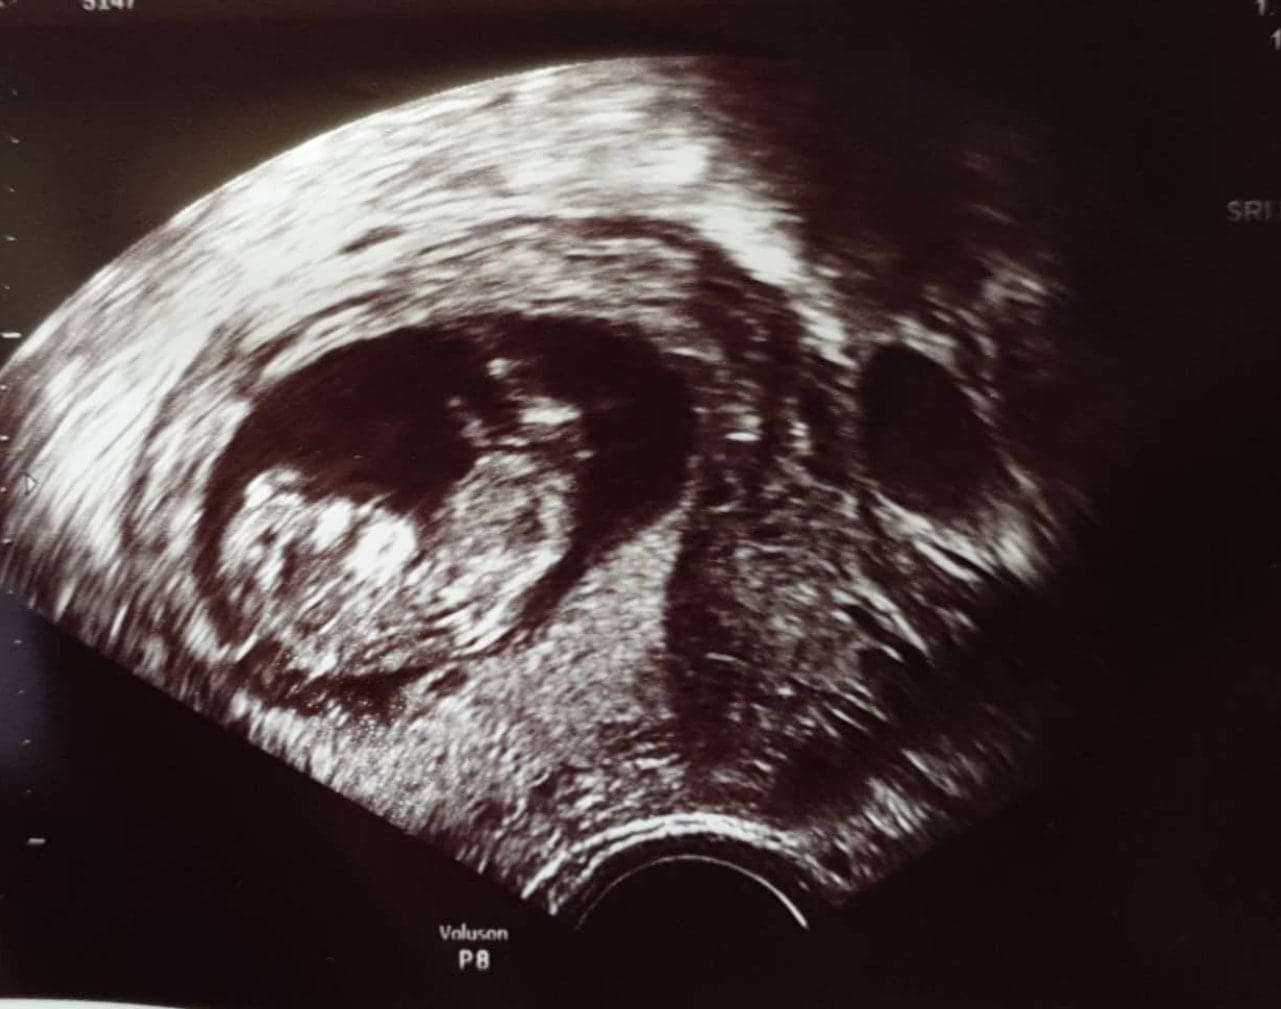

Ultraschallbilder aus dem 2. Trimester (13. bis 28. SSW)

Im 2. Trimester bekommt man oft die schönsten "Ganz-Körper" Ultraschallbilder. Das Baby ist nun so groß, dass man alles gut erkennen kann und noch nicht zu groß, so dass es noch ganz auf das Bild passt. In dieser Zeit lässt sich meist das Geschlecht bestimmen, wobei manche Babys es einfach nicht preis geben wollen und sich immer so drehen, dass man nichts erkennen kann.